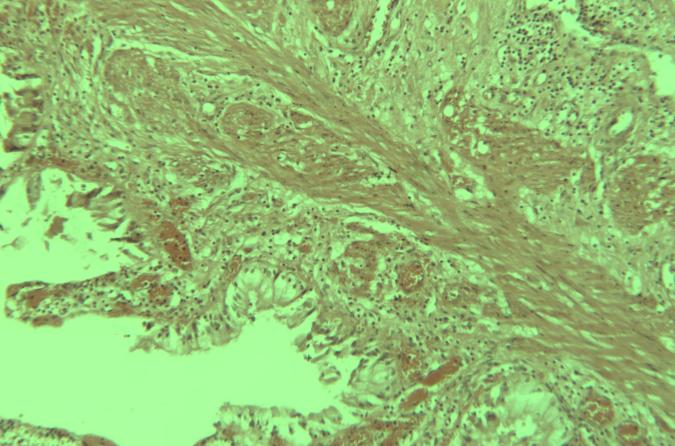

ÔÚĘšĶÃÃ÷ÃĀšâëī@ÎĸįRŗÉĪņÜŧūŖ¨MShot Image Analysis SystemŖŠrŖŦĶÃôŗŖūĶöĩŊÜŧūŗÉĪņąŗž°îÉĢÅcÄŋįRĪÂĶ^˛ė˛ģŌģÖÂĩÄî}ĄŖąžÎÄáĻß@ŌģŦFĪķŖŦĖᚊĪĩŊyĩÄÔŌōˇÖÎöÅcŊâQˇŊˇ¨ŖŦ˛ĸ¸ŊÉĪ˛Ų×÷×ĸŌâĘÂíŖŦÍÖúĶÃô¸ßЧÍęŗÉîÉĢĐŖÕũĄŖ

î}ŦFĪķŖēŗÉĪņąŗž°îÉĢŽŗŖ

ĶÉĶÚī@ÎĸįRšâÔ´ÅcĪāCÄŦÕJÔOÖÃĩIJîŽŖŦÜŧūŗÉĪņąŗž°ŋÉÄÜŗöŦFÆĢÉĢŖ¨Čį°lüSĄĸˇēË{ĩČŖŠŖŦČįD1ËųĘžĄŖ´Ëîî}ŲĶÚÕũŗŖŦFĪķŖŦŋÉͨß^ÜŧūČÖÚ¤žßŋėËŲĐŖÕũĄŖ